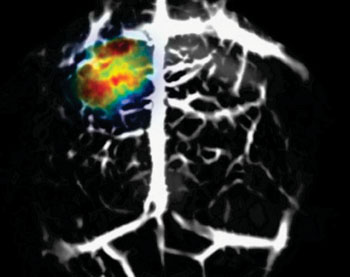

Tomografía fotoacústica y Deep Learning en aplicaciones médicas

En las últimas décadas, las imágenes fotoacústicas han demostrado su eficacia en el apoyo al diagnóstico de algunas enfermedades, así como en la investigación médica, ya que a través de ellas es posible obtener información del cuerpo humano con características específicas y profundidad de penetración, desde 1 cm hasta 6 cm dependiendo en gran medida del tejido estudiado, además de una buena resolución. Las imágenes fotoacústicas son comparativamente jóvenes y emergentes y prometen mediciones en tiempo real, con procedimientos no invasivos y libres de radiación. Por otro lado, aplicar Deep Learning a imágenes fotoacústicas permite gestionar datos y transformarlos en información útil que genere conocimiento. Estas aplicaciones poseen ventajas únicas que facilitan la aplicación clínica. Se considera que con estas técnicas se pueden proporcionar diagnósticos médicos confiables. Es por eso que el objetivo de este artículo es proporcionar un panorama general de los casos donde se combina el Deep Learning con técnicas fotoacústicas.

Vea el texto completo en:

Sánchez-Medel N, Zétera-Díaz J, Díaz-Hernández R, Altamirano-Robles L. Tomografía fotoacústica y Deep Learning en aplicaciones médicas. Revista Cubana de Informática Médica [Internet]. 2023 [citado 13 Nov 2023]; 23 (2).